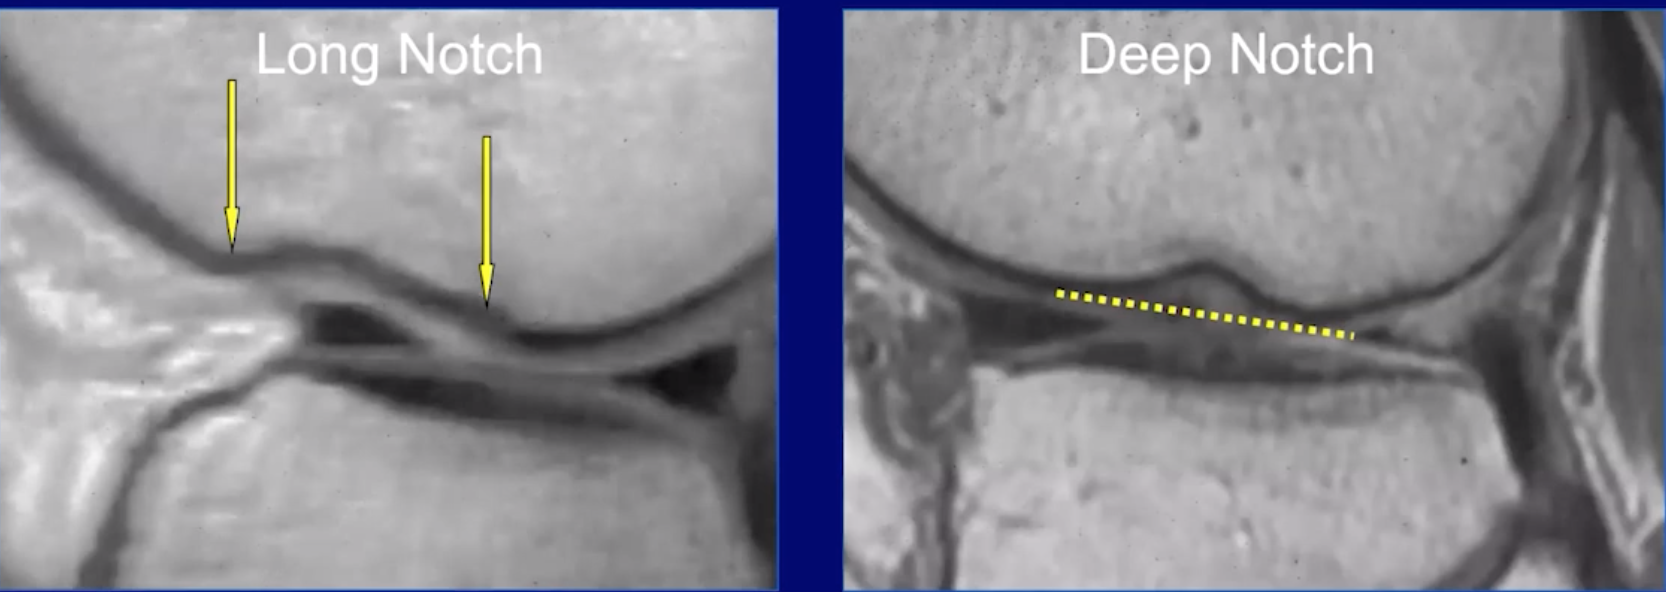

• Notch sign

• Deepening of the normal groove in the lateral femoral condyle

• > 2mm is diagnostic of acute or chronic tear